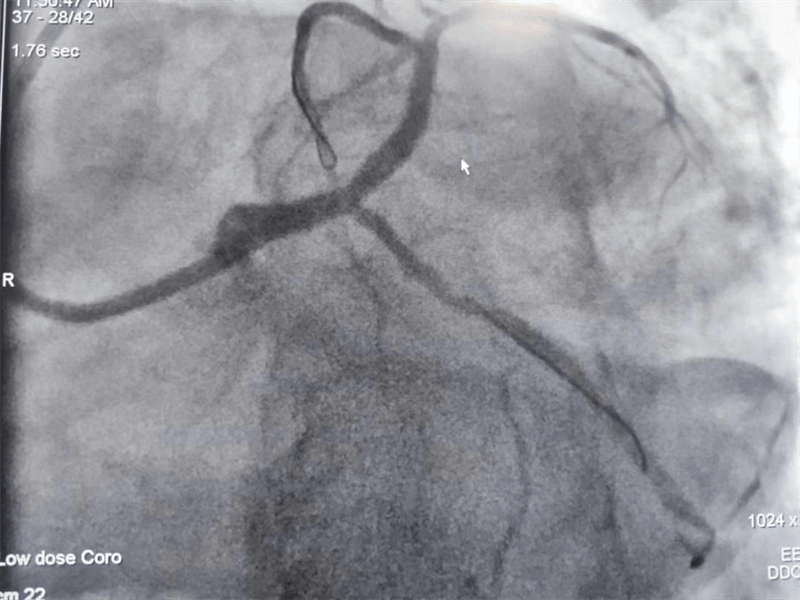

冠脈造影結(jié)果提示:左主干末端及前降支開口處99%狹窄,回旋支開口處80-90%狹窄,中段支架內(nèi)100%閉塞??吹皆煊敖Y(jié)果時(shí),在場(chǎng)醫(yī)護(hù)人員無(wú)不驚出一身冷汗:左主干病變“細(xì)”如發(fā)絲——生死一線牽!患者拒絕搭橋手術(shù),所以選擇介入處理該病變。

患者在冠脈造影檢查術(shù)中,感到胸悶、胸痛發(fā)作,血壓下降、心率減慢,我們立即對(duì)左主干狹窄段進(jìn)行球囊擴(kuò)張后癥狀好轉(zhuǎn),生命體征逐漸平穩(wěn)。